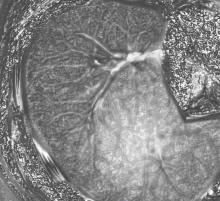

This is an example of Canon's Advanced intelligent Clear-IQ Engine (AiCE) AI-driven image reconstruction software that is now being used to improve image quality on the Canon Celesteion Prime PET/CT nuclear imaging system. The deep learning is used to enhance the iterative reconstruction used to reduce noise and sharped high contrast resolution on positron emission tomography (PET) images from the digital PET detector used on the system.

This example is a whole-body FGD PET scan of a patient with a large BMI with lung cancer.

The Cartesion Prime PET/CT is the industry’s only air-cooled digital PET/CT, provides variable bed time (vBT) acquisition as a standard feature. This and the new FDA 510(k)-pending AiCE technology were highlighted at the 2020 Radiological Society of North America (RSNA) virtual meeting.